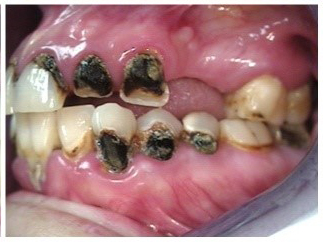

Often, the most visually striking manifestation of long-term meth use—known as “meth mouth”—is caused by the lack of saliva combined with an increase in soda drinking and extremely poor oral hygiene. This typically leads to meth abusers experiencing a large amount of caries. Decay begins with occlusal and facial caries and progresses rapidly, decaying to the bone level and often leaving only roots (Figure 1 through Figure 3).16

Fig 2. Gross oral destruction was the result of more than 20 years of meth use in this 41-year-old woman.

Figure 2